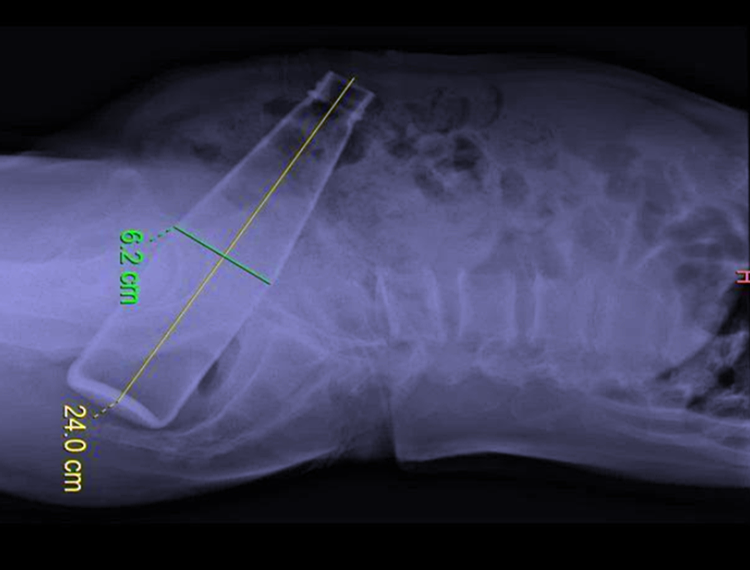

【热点趣事|难以启齿的手术:河南奇葩男子把一个24CM玻璃瓶塞进肛门里,自取一个晚上未果羞愧送医】据说是“不慎” , 结果是硬生生把一个玻璃饮料瓶子从肛门里塞了进去 , 瓶子长有24CM , 直径6CM , 好家伙!这么大的瓶子塞进肛门 , 老毕究竟想干啥事?瓶子进入身体后 , 老毕本想自己把它拿出来 , 一个人在卫生间里苦苦努力“奋斗”了一个晚上 , 最后还是以失败告终 。 因为他的错误努力 , 以至于瓶子进入人体的更深位置 , 老毕害怕了 , 红着脸把事情告诉了家人 , 当时家人一脸懵逼 , 搞不懂他在干什么 。

肛肠科团队通过与病人家属沟通 , 制定了两套医治方案 , 首先由麻醉师协助 , 先从肛门尝试直接取出玻璃瓶 , 如果尝试失败 , 立即实施第二套方案 , 手术从腹腔取出 , 切实做到有备无患 。 随后 , 老毕就被推进了手术室 , 肛门内取瓶子开始 , 副主任医师的手最小 , 由她用手探查玻璃瓶的具体位置 , 然后主任根据她的提示 , 用手在病人的腹部渐渐挤压 , 缓缓地将瓶子推向直肠末端 , 随后 , 采用肛门扩撑器撑开肛门 , 再用手术器械吸住瓶子慢慢向外牵引 。

经过多位医生的共同努力 , 大家各司其职 , 用了一个多小时时间 , 终于把玻璃瓶从老毕肛门里取了出来 , 最终没有用到第二套方案 , 老毕住院了3天 , 感觉身体已经无大碍 , 就办理了出院手续 , 满脸羞愧地回到了家里 。 不过 , 至于他为什么要把一个那么大的瓶子强行塞进肛门 , 他没有说 , 但不管怎样 , 这事是有惊无险 , 相信老毕吃了这次大亏 , 往后不会再胡来的了 。 这起奇葩事件被网络曝光后 , 网友除了哈哈大笑外 , 也展开了猜测大讨论:他为啥要塞个瓶子?